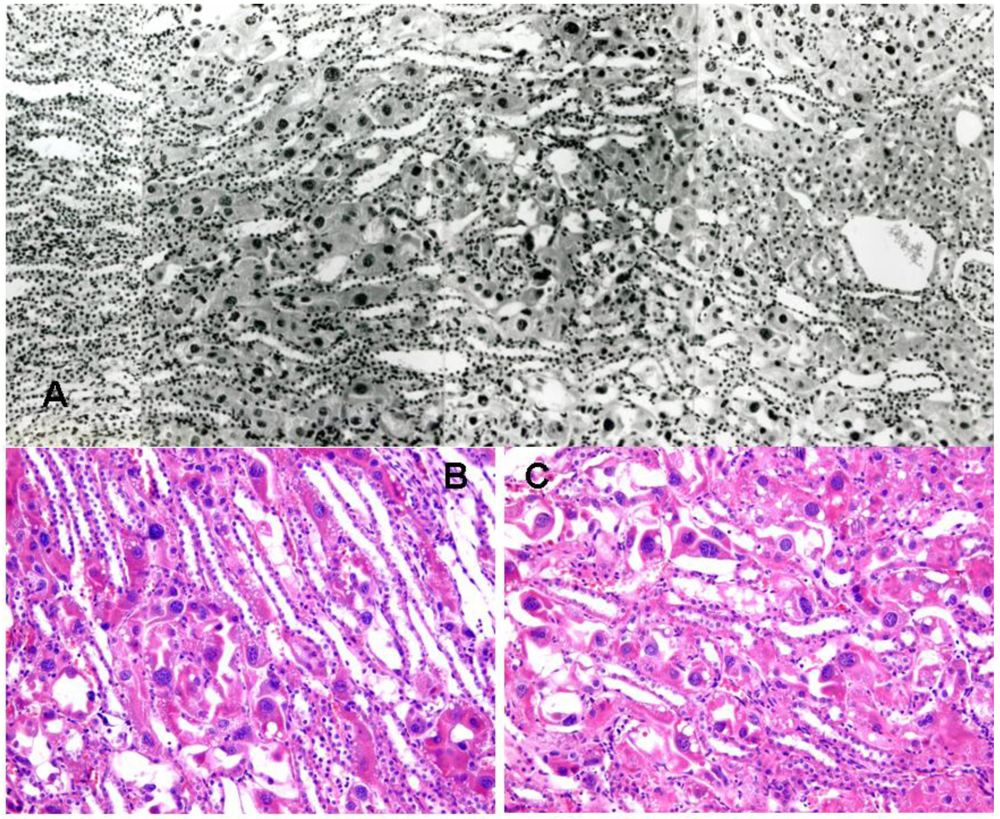

Rat renal histopathology (stained with H & E) after five weeks on a P. polonicum-contaminated diet (rat 4). A, part of saggital section traversing from innermost glomerulus in cortex (right) into the medulla, showing extensive, diffuse karyocytomegaly across the region. B and C, two representative examples in the region associated with concentration of P3 segments of nephrons, showing detail of enlarged nuclei in distorted cells.

A similar degree of diffuse histopathological change was produced in rat 2 by giving similarly in feed a small sample of the extract from the remaining 59 flasks, most of which was used later for the primate. The total amount of extract given to rat 2 over the four days represented 28 g of shredded wheat culture, implying ~95% efficiency in retaining the nephrotoxin(s) through selection of a fraction of alcohol-soluble and cation-exchangeable components of the fermented cereal substrate. Increasing the dose of extract five-fold for rat 3 only gave slightly greater incidence of the characteristic histopathological change, indicating that the lower dose was already near maximum for effect.

3.2. Rat: Renal histopathology after five, ten or sixty-six weeks on a diet containing a 20% component of shredded wheat moulded by P. polonicum

In rat 4, after five weeks on the P. polonicum-contaminated diet, the karyomegaly seen clearly in rats 1–3 above after four days had progressed in magnitude and frequency to the striking karyocytomegaly illustrated in Figure 1. After ten weeks treatment for rat 5, unilateral nephrectomy provided tissue for histology showing further progression of karyocytomegaly while mitotic events continued (Figure 2 A, B). Monitoring body weight in rat 5 (Figure 3) showed that P. polonicum was well tolerated for a total of 463 days since first exposure. Permanent transfer then to normal feed coincided with foot lesions caused by maintaining a heavy animal on paper, reflected in the temporary decline in body weight (Figure 3) while lesions healed. Notably, fertility was confirmed 693 days after P. polonicum exposure commenced (25 months of age); five weeks later the rat was found moribund and euthanized. The only notable feature at necropsy was the remaining kidney (9.4 g, 3.3 cm long axis), much enlarged at least to compensate for the previous unilateral nephrectomy. The kidney surface implied extensive cysts, which are commonly a feature of ageing. Histology revealed the cysts, and persistent karyocytomegaly in the cortico-medullary region, but there was no evidence of tumour.